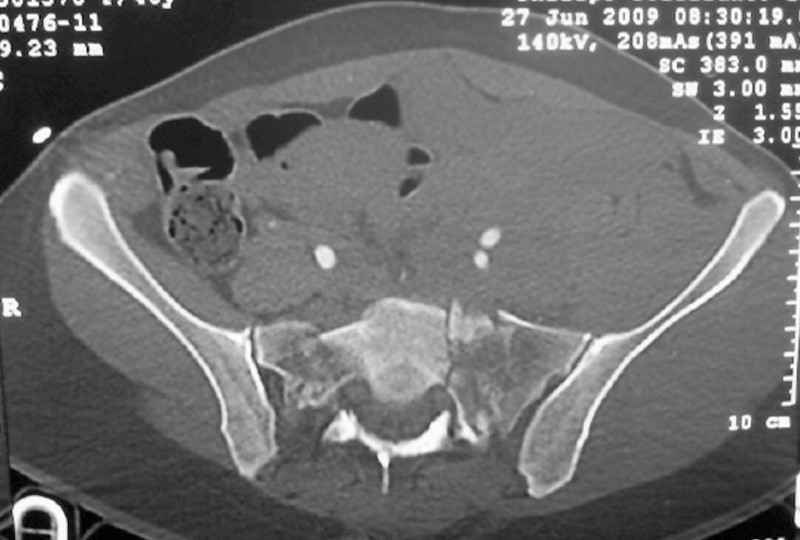

General condition is fine except for an intractable pelvic pain, no associated injuries (only ankle fracture), no sciatic nerve injury.

The soft tissues are also in mild condition, buttock hematoma and probably a Morel-Lavalle. I send some more CT images. There are some conminution in the posterior column (I don’t have images now). The patient is scheduled for surgery next Monday. The plan is percutaneous sacral fixation and then ilioinguinal approach .